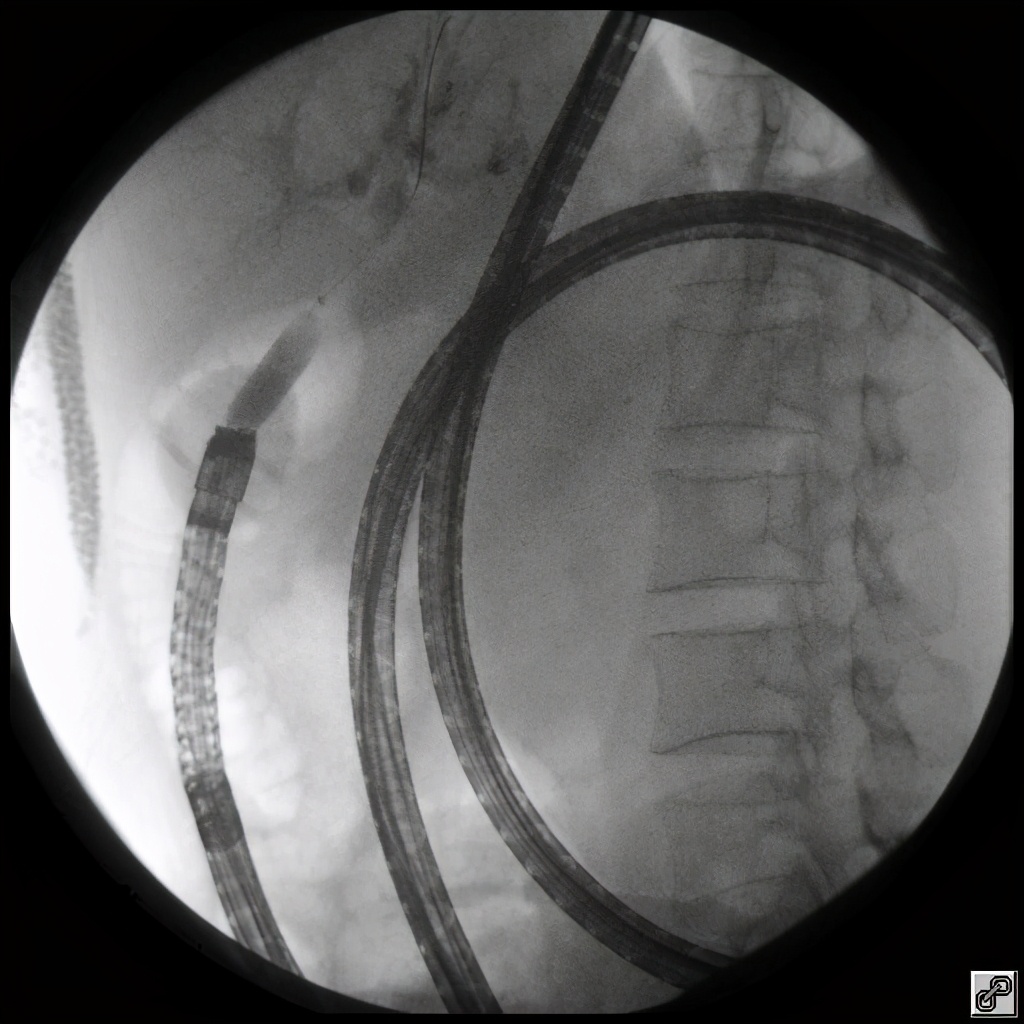

(对狭窄的胆肠吻合口进行扩张)

医生决定使用双气囊小肠镜辅助操作,行内镜逆行胰胆管造影术,也就是传说中的 ERCP。

双气囊小肠镜辅助ERCP技术的出现,为上消化道改道术后患者进行ERCP治疗提供新的思路,使患者免于再次外科手术,其操作难度较常规ERCP大大增加。